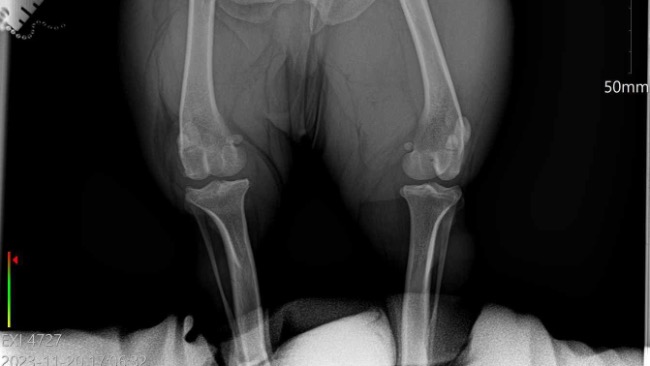

Początkowo pojechalam z partnerem do weterynarza ktory po konsultacj z nami i zbadaniu pieska podejrzewał zerwanie więzadła krzyżowego. Weterynarz skierował nas na prześwietlenie łapki oraz badania krwi do Dr. Gierek w Katowicach. Niestety obawy naszego weterynarz się potwierdziły okazało się ze musi mieć jak najszybszą operacje ponieważ gdy nie zoperujemy zerwanego więzadła piesek będzie cierpiał i jednocześnie obciążał mocno druga tylnią łapkę i może dojść do zerwania więzadła w drugiej łapce a wtedy nasz piesek już nie będzie mógł biegać.

Całą zebrana kwotę przekażemy na operacje naszego psiaka. W załączniku udostępnione są wyniki oraz zdjęcie łapki